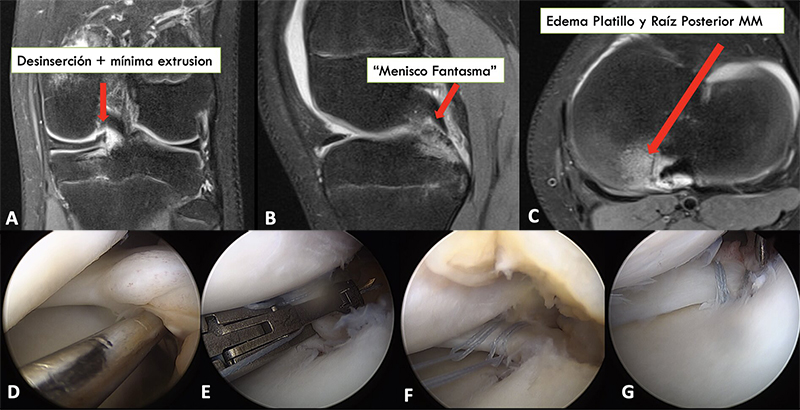

Figura 2: Paciente de 13 años, torsión de rodilla jugando fútbol. Resonancia magnética evidencia. A) Corte coronal con imagen sugerente de lesión de la raíz posterior del menisco medial, con mínima extrusión meniscal. B) Corte sagital, ausencia de la raíz posterior del menisco medial, signo conocido como “menisco fantasma”. C) Corte axial, edema del platillo y raíz posterior medial. D) Visión artroscópica, se confirma la desinserción completa de la raíz meniscal medial posterior. E, F y G) Pasos en la reparación de la raíz, utilizando dos suturas de tracción de alta resistencia, y un túnel transtibial en el punto centro anatómico de la raíz meniscal medial.